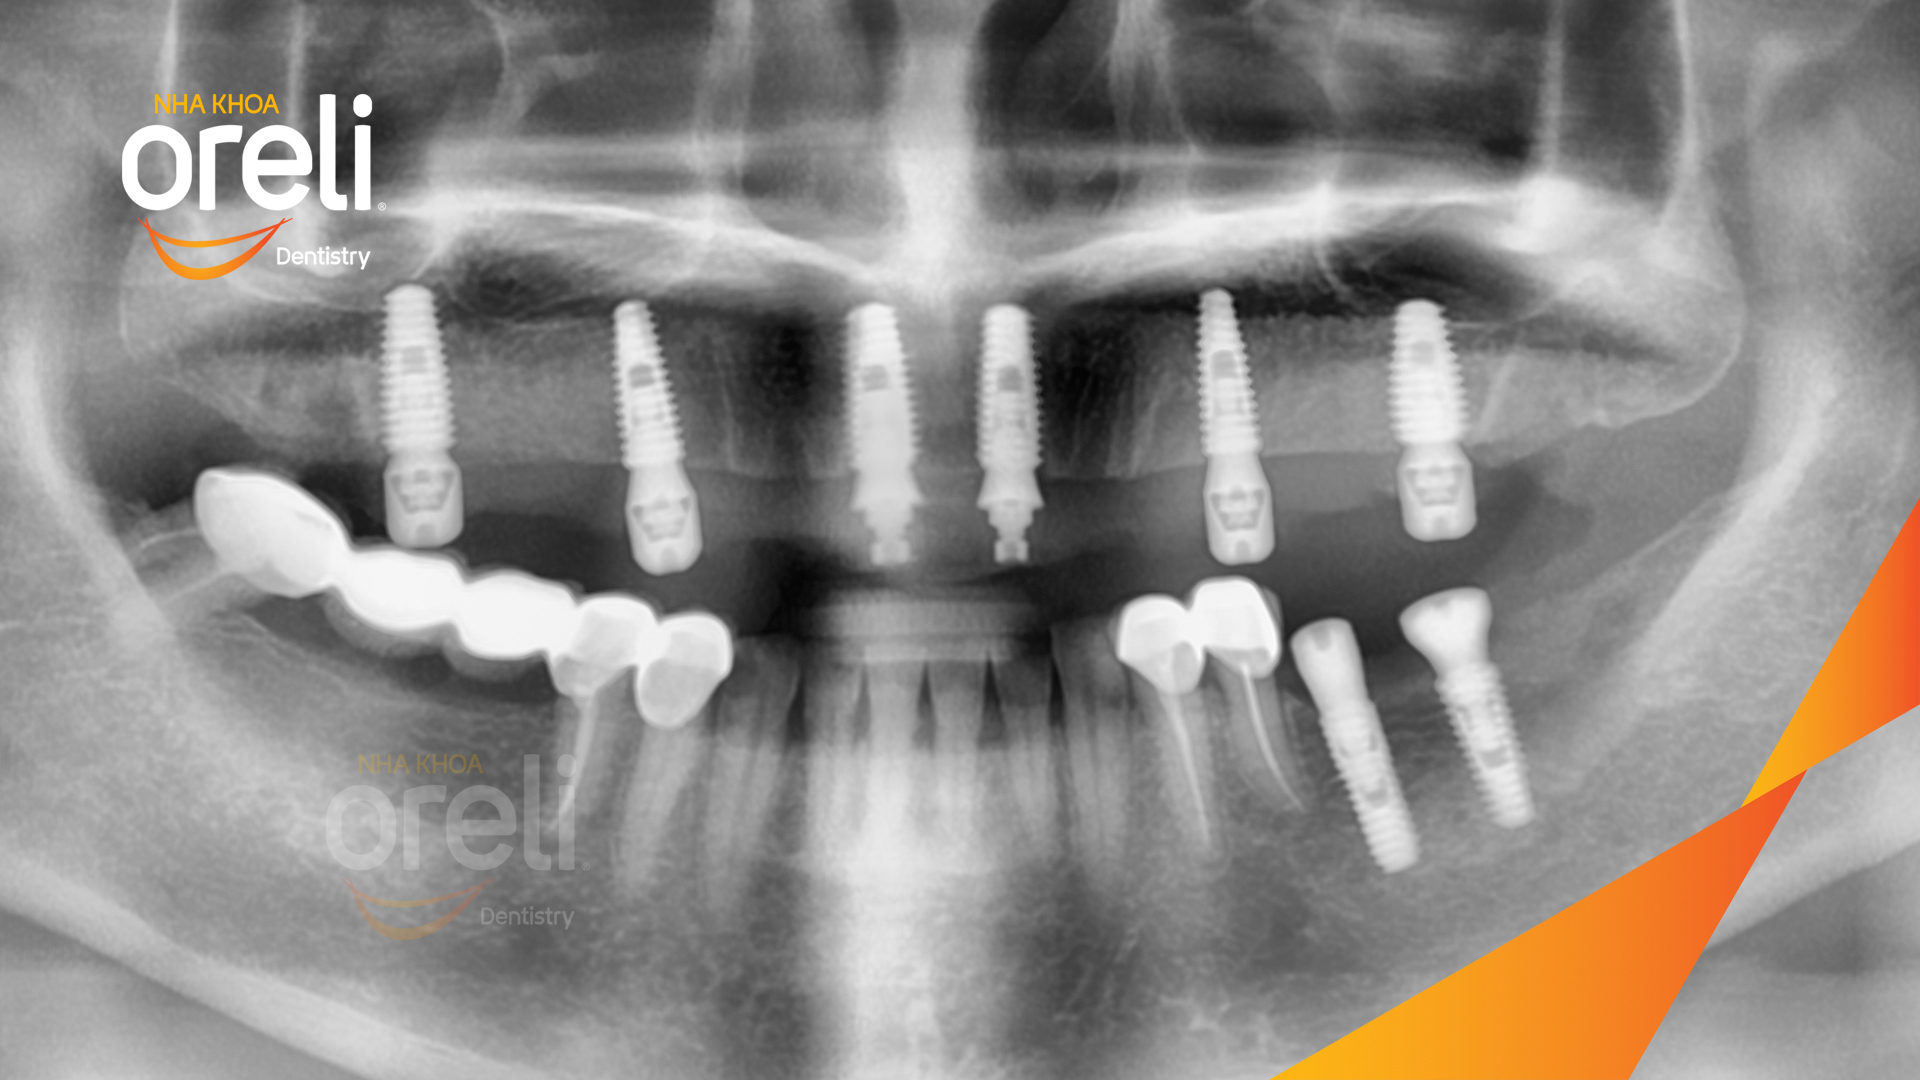

Tình trạng: Cầu răng sứ hàm trên lâu ngày gãy, viêm nướu, chân răng lung lay

Giải pháp: Cắt cầu răng sứ, nhổ răng, trồng răng implant

Hình ảnh thực tế